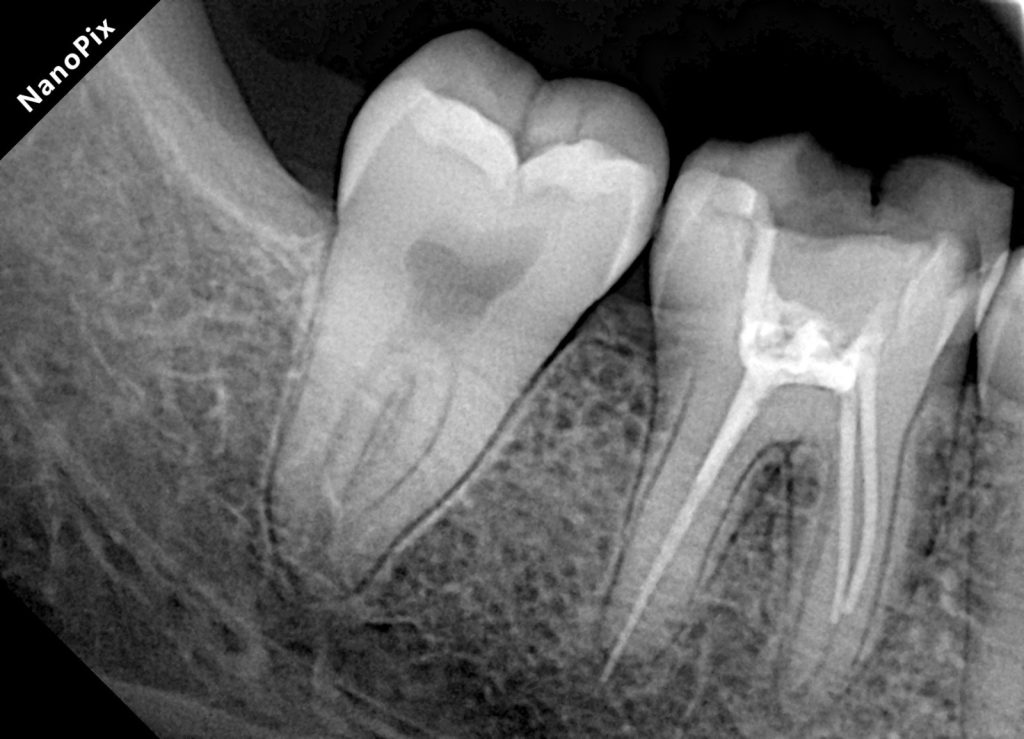

Patient presented with pain on biting and food packing around a previously treated molar. The radiograph showed under-prepared canals, missed anatomy, poor obturation density, and a failing coronal seal. Distal wall was undermined and cracked.

- Previous RCT failure: Voids, short fill on one canal, coronal leakage.

3. Warm Vertical Compaction – True 3D Fill

- Canals dried with paper points.

- Bioceramic sealer applied sparingly using micro brush.

- Downpack: System B heated plugger carried to 4–5 mm from apex.

- Backfill: Injected GP to crest, continuous wave technique.

- Clear 3D fill visible in postoperative radiographs.

- Clean radiographs with excellent obturation length and density